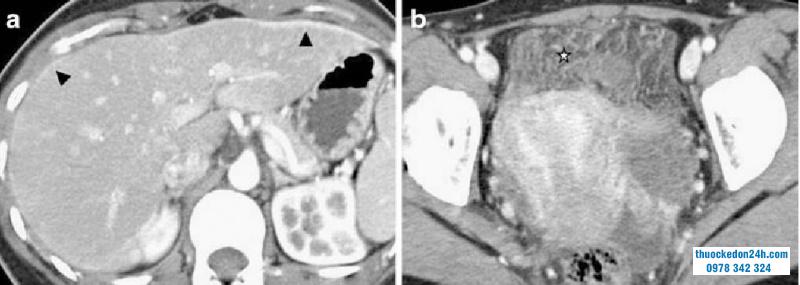

Bệnh nhân nữ 26 tuổi đau hạ sườn phải và sốt nhẹ, nhập khoa cấp cứu. (a) CT thì động mạch cho thấy viêm bao gan lan tỏa (đầu mũi tên) bắt thuốc dọc phần trước ngoài gan. (b) CT vùng chậu cho thấy thâm nhiễm mỡ phúc mạc và phần trước khoang chậu (dấu sao), phù hợp với viêm nhiễm vùng chậu.

Phương tiện hình ảnh CT Scan sẽ biểu hiện viêm nhiễm ở vùng chậu và vùng quanh gan. Cụ thể:

Với vùng chậu: Có thể cho thấy một áp xe phần phụ, ứ mủ vòi trứng, dịch vùng tiểu khung.Với vùng quanh gan: Có thể thấy các dải viêm, dịch dọc rãnh đại tràng phải và quanh gan, bắt thuốc bao gan, dày thành túi mật, thay đổi viêm quanh đường mật, bất thường tưới máu nhu mô gan thoáng qua.